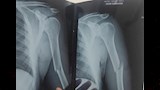

أعلنت مديرية الصحة بالمنيا، عن نجاح فريق طبي في إجراء عملية جراحية دقيقة وناجحة داخل مستشفى الصدر، لشاب يبلغ من العمر 22 عامًا، يعاني من مرض العظم الزجاجي (Osteogenesis Imperfecta)، وهي حالة وراثية نادرة تجعل العظام شديدة الهشاشة وعرضة للكسور المتكررة.

ووفقًا لبيان المديرية، فقد تعرّض الشاب لحادث أدى إلى كسر في العضد الأيمن، وعلى الفور جرى نقله إلى المستشفى، وتم تثبيت الكسر بنجاح باستخدام شرائح ومسامير.